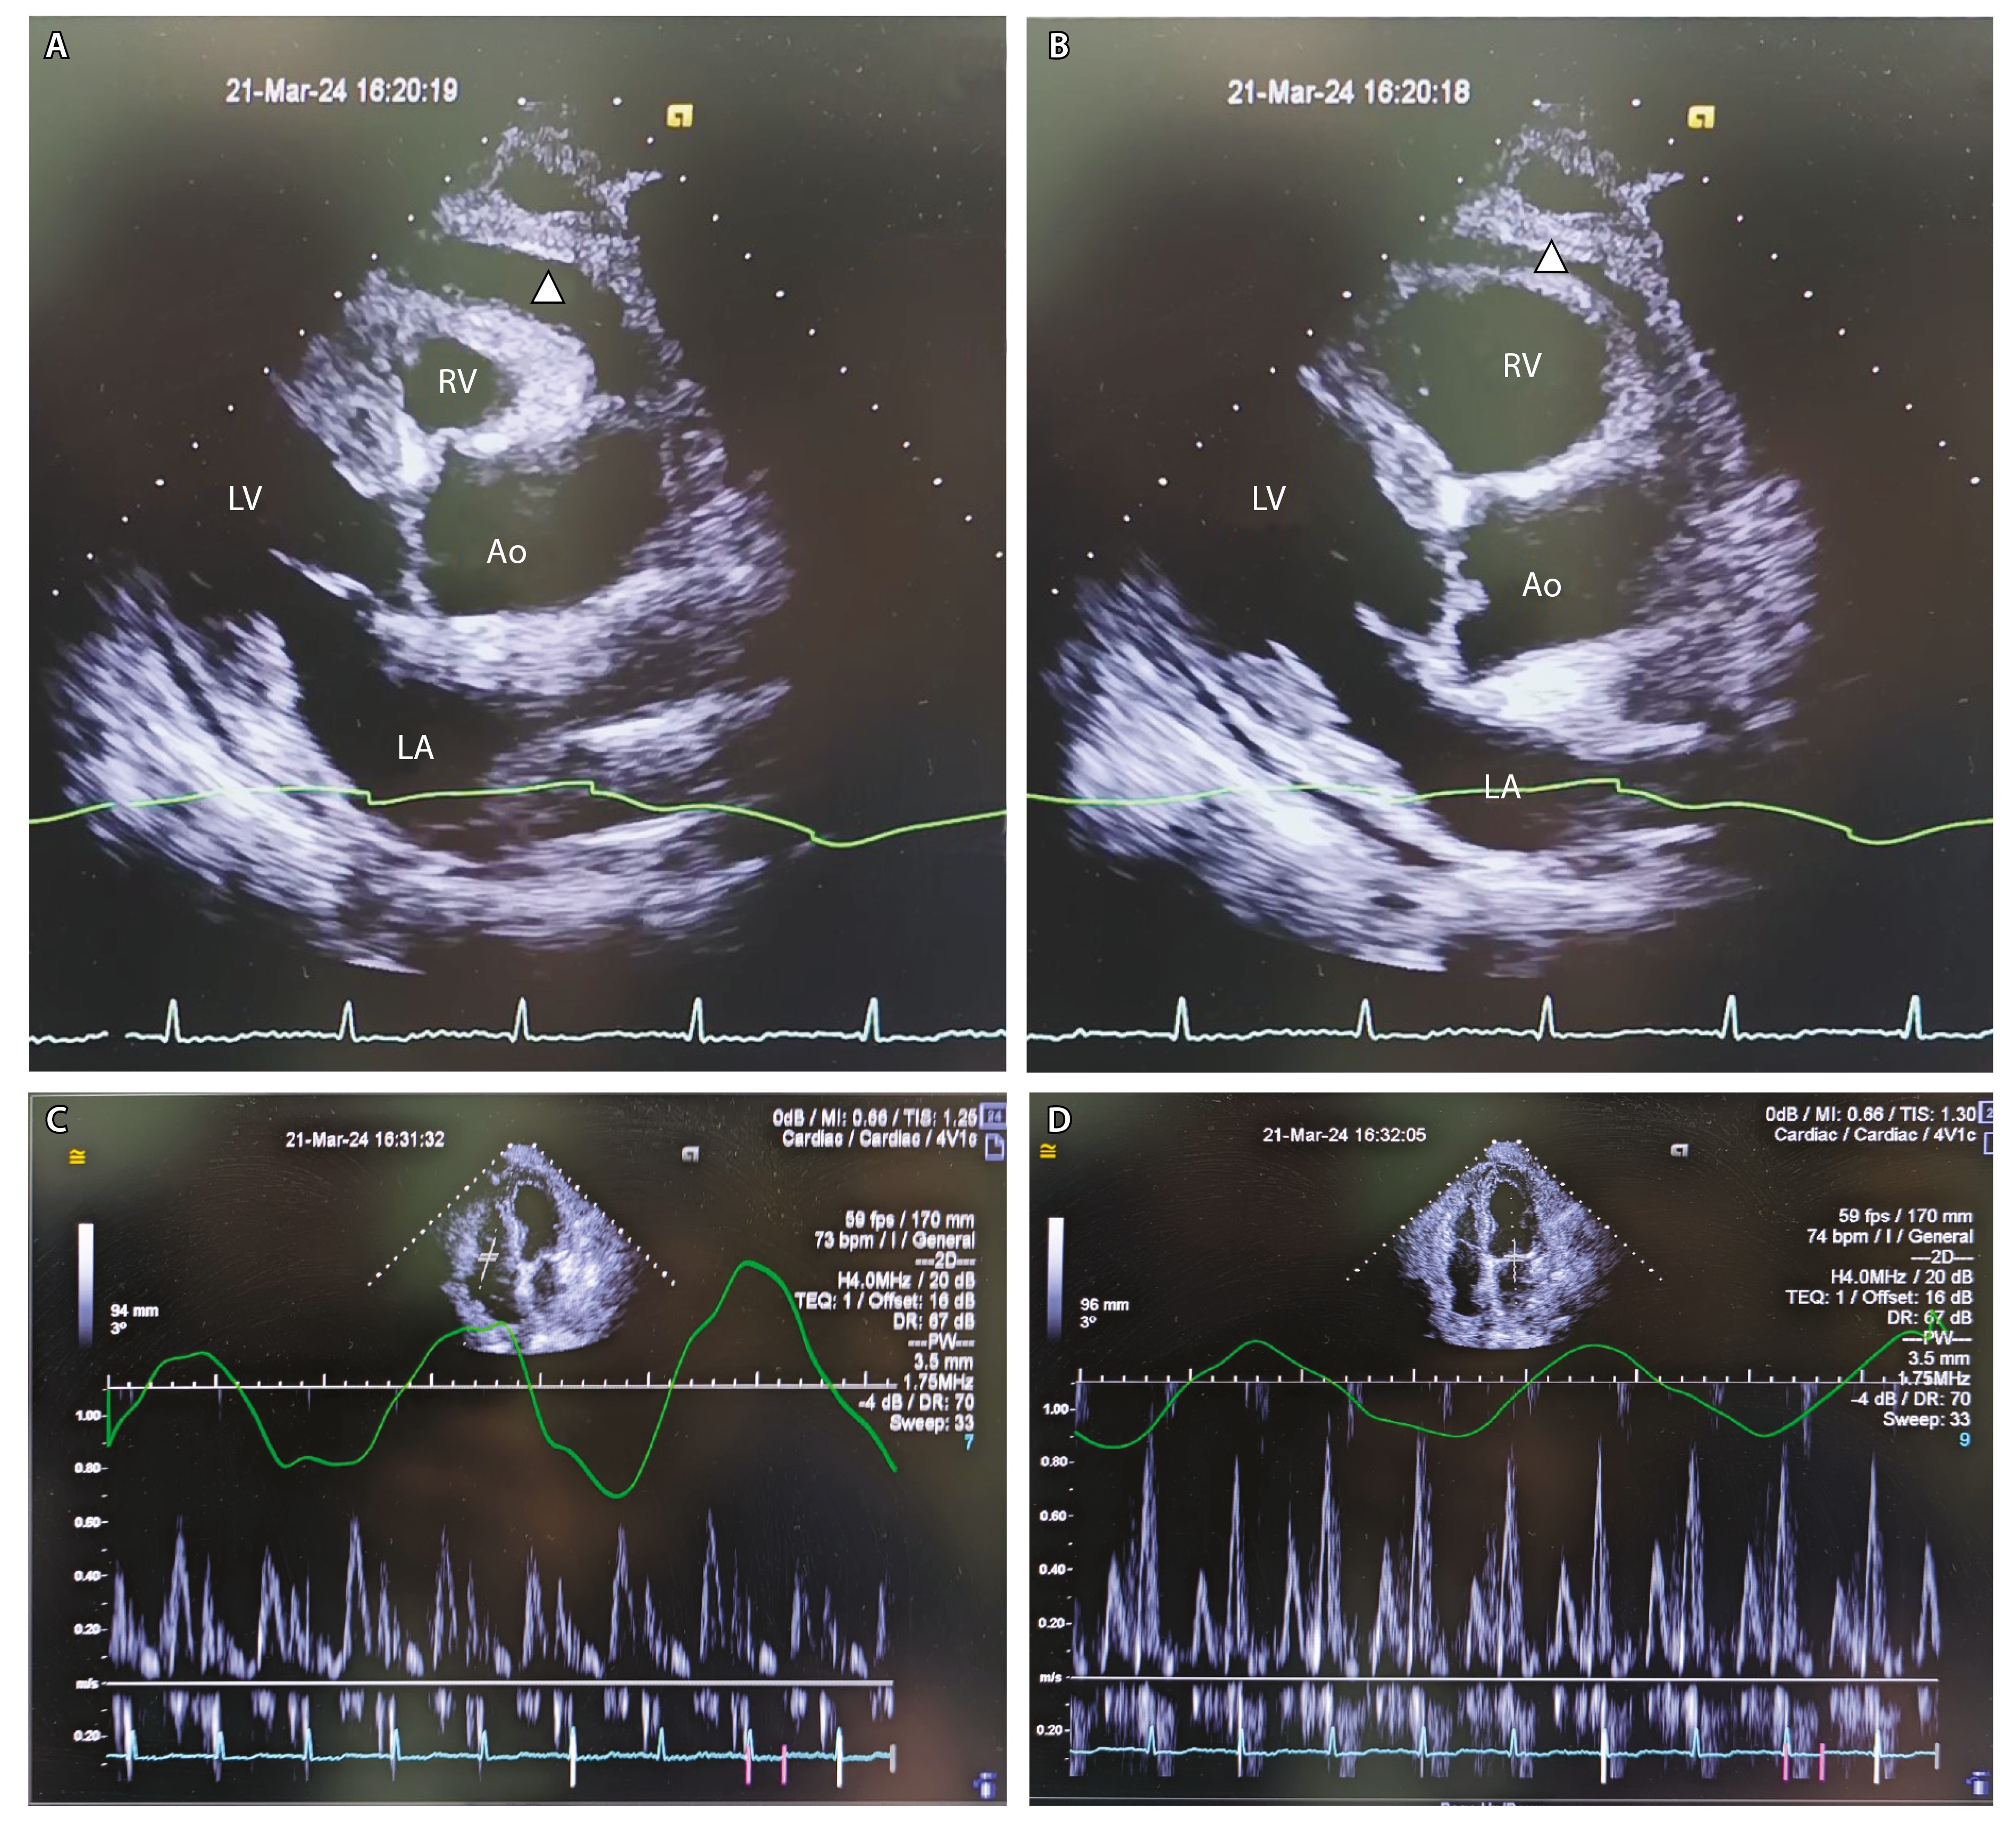

Повторно проведена Эхо-КГ (21.03.2024, рис. 3). По сравнению с предыдущим исследованием ФВ – 46%. Отмечается «дрожание» межжелудочковой перегородки. Отсутствует скользящее движение перикарда в области верхушки и боковой стенки ЛЖ. Количество жидкости в полости перикарда небольшое, без значимой динамики в сравнении с предыдущим исследованием: за задней стенкой ЛЖ – до 8 мм, над ПЖ – до 6 мм, диастолического коллапса ПЖ нет. При доплеровском исследовании – выраженное изменение скорости кровотока от фаз дыхания: на вдохе скорость трансмитрального кровотока снижается более чем на 25%, транстрикуспидальный кровоток повышается более чем на 25%. Выраженная дилатация НПВ – диаметр 34 мм, на вдохе не коллабирует. Диастолическая функция миокарда нарушена: E/A – 0,8, Elat – 10 см/с (N > 10 см/с), Emed – 8,7 см/с (N > 7 см/с), E'lat/E'med – 1,16 (N > 1,2, annulus reversus). Выявленные изменения свидетельствовали о том, что ведущим механизмом одышки и отеков у пациента была констрикция – ограничение подвижности миокарда выпотом и ригидным перикардом [14].

Рис. 3. Эхокардиограмма пациента: А – парастернальная позиция, длинная ось ЛЖ, систола; Б – парастернальная позиция, длинная ось ЛЖ, диастола; В – доплеровское исследование транстрикуспидального кровотока; Г – доплеровское исследование трансмитрального кровотока. Ао – аорта, ЛЖ – левый желудочек, ЛП – левое предсердие, ПЖ – правый желудочек. Белый треугольник указывает прослойку жидкости в перикарде